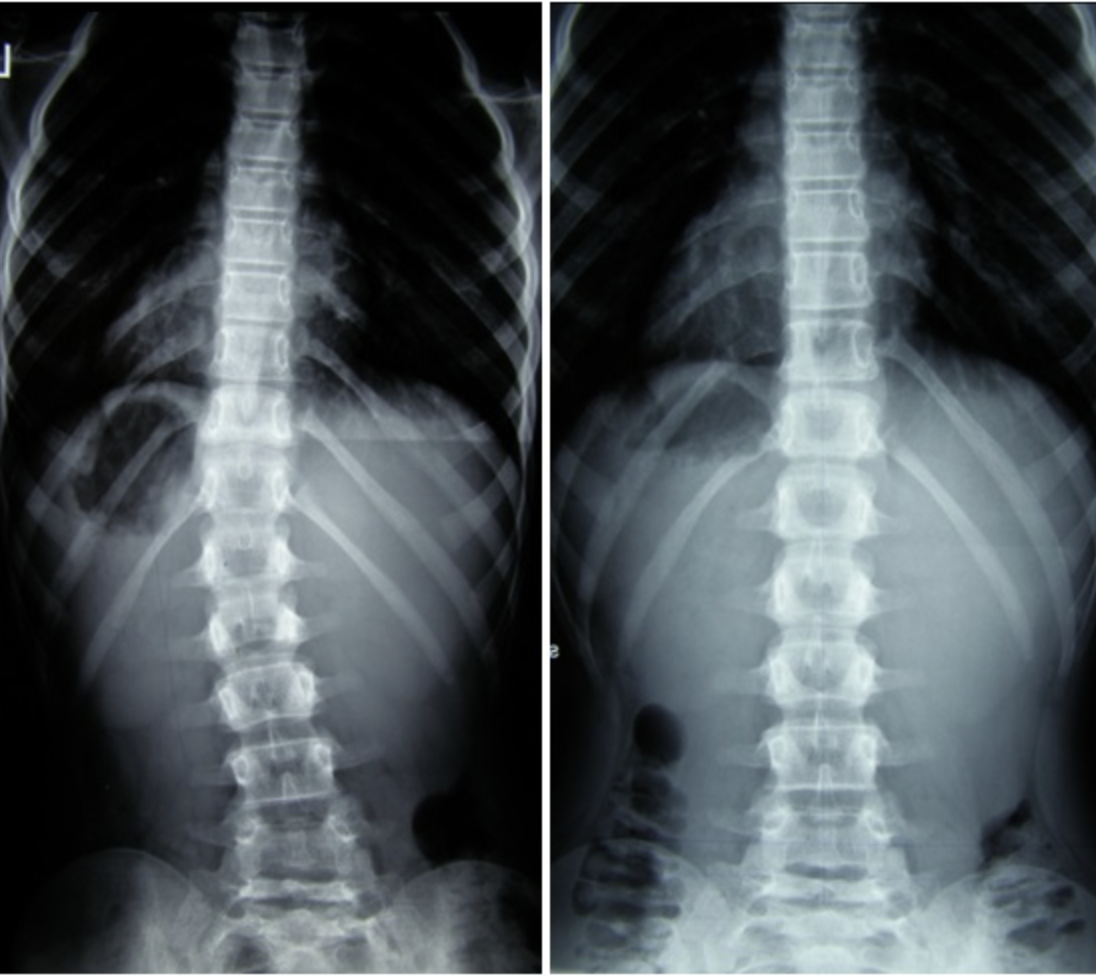

Piotr - 10 lat Terapia prowadzona w okresie 15.09 – 01.12.2008 (20 zabiegów) Częstotliwość zajęć –...